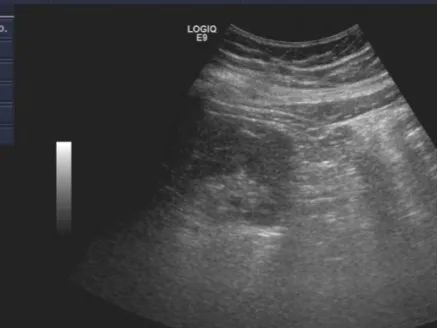

超声引导下肾穿刺后肾周血肿

近日,新医大一附院肾脏疾病中心肾病二科收住了两名病情复杂的患者:一名患者存在孤立肾(右肾缺如)的情况,另一位则因肾功能快速衰退、肌酐水平高,且超声探查下其肾脏显著弥变、皮髓界限不清,皮质厚度0.7cm,急需进一步明确诊断但既往同类病人出血率极高,都属于超声引导下肾活检的禁忌。